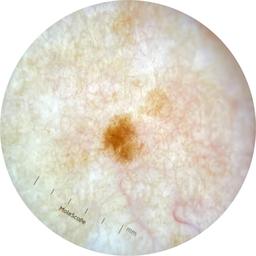

ISIC_9097190

2049 x 2049

acquisition_day 181

age_approx 45

anatom_site_1 Trunk

anatom_site_2 Anterior trunk

anatom_site_general anterior torso

diagnosis_1 Benign

image_type dermoscopic